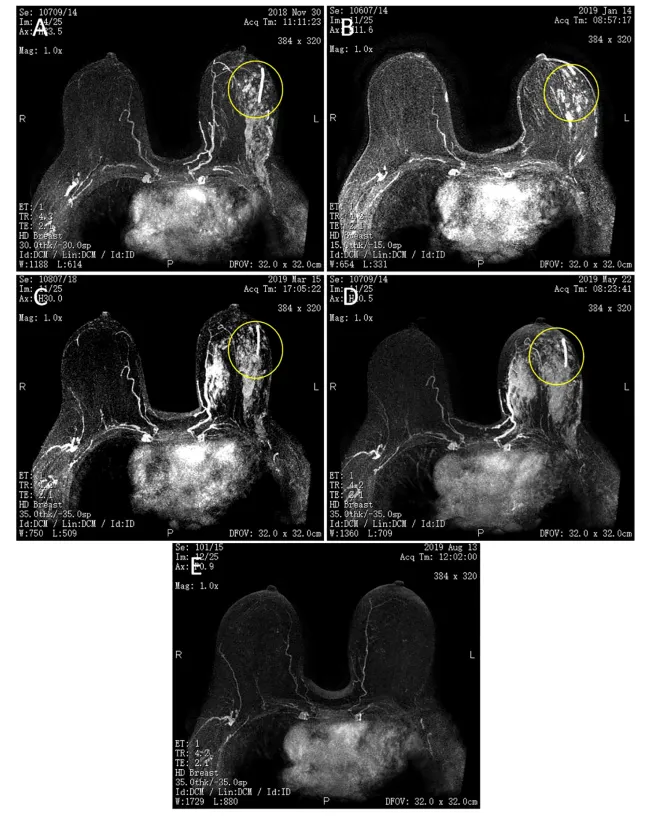

图1:双侧乳腺磁共振成像(MRI)。(A)TEC*2.(B)TEC*4.(C)NP*2.(D)NP*4.(E)卡培他滨+氟维司群3月+,左侧乳腺病灶消失。黄色圆圈表示左乳房病变。

根据《中国乳腺癌新辅助治疗专家共识(2017年版)》,患者于2018年10月接受TEC方案新辅助治疗。4个周期后根据实体瘤疗效评价标准(RECIST)1.1版进行临床疗效评价疾病稳定(StableDisease,SD)。再次对原发灶进行空芯针穿刺活检,病理显示左乳浸润性导管癌,Ⅰ级,ER(+,60%)、PR(–)、HER2(1-2+)、Ki-67(40%)。遂于2019年1月开始更改为NP方案(长春瑞滨40mg+卡铂500mg)。化疗5次后病灶大致同前,疗效评价仍为SD并伴有Ⅲ级骨髓抑制。鉴于患者前后使用2次不同化疗方案治疗后效果均不佳,且患者不能耐受继续化疗,经全科讨论并与家属充分沟通意见后,于2019年5月开始使用卡培他滨联合氟维司群治疗。治疗方案为口服卡培他滨1000mg/m2口服早晚各1次,吃2周停1周;FUL 500mg,肌注,初始阶段每隔2周1次,连续3次,维持阶段每月1次。令人惊喜的是,经这种改进后的联合方案治疗后,患者的乳腺原发灶和淋巴结均缩小(图1),同时血清肿瘤标志物降至正常(图2)。后续其他相关检验及检查均未见异常,3+月后临床疗效评价肿瘤完全缓解(Complete response,CR)。